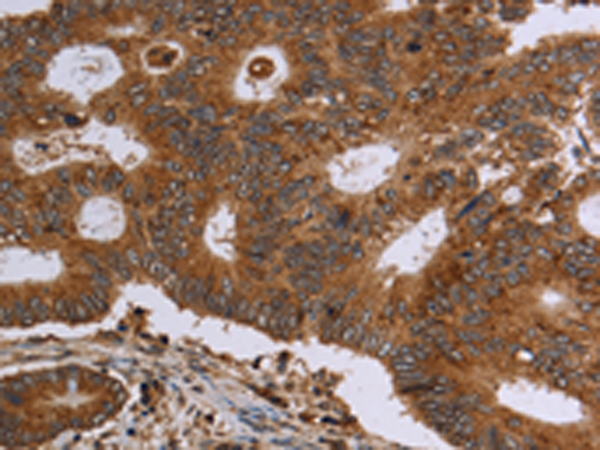

分类: 科研抗体货号: P08400别名: KMT7; SET7; SET9; SET7/9应用: IHC反应种属: Human, Mouse